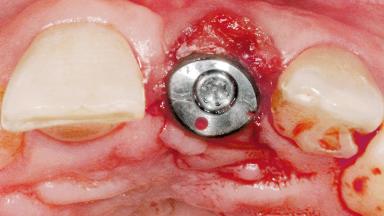

Late Flapless Placement of an Implant in a Maxillary Left Central Incisor Site

A 39-year-old male patient presented with a chief complaint of discomfort and gingival discoloration around his maxillary left central incisor. He was in good general health and was a non-smoker. His past dental history was significant because of the traumatic fracture of tooth 21 in a sporting accident at age 13. Initial dental treatment included endodontic therapy and a full-coverage restoration. The patient became symptomatic 5 years later, when structural failure of the tooth resulted in the dislodgment of the crown. Endodontic retreatment, apical surgery, and post-and-core restoration were performed.

Placement Protocol Early or late implant placement

Bone Volume Deficient horizontally, requiring prior grafting